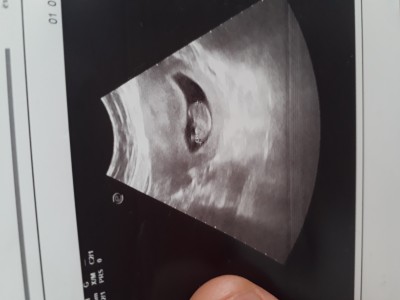

Daha çok küçüğüz ama cinsiyet tahmini yapabilir misiniz? :)

Crl den cinsiyet yazan bayan vardı o görür inşallah. Benimkini doğru bilmişti

Crl niz nedir cnm eger dusukse erkek yuksekse kiz diye duymustum  ve bende tuttu bzmki 5. Kusurdu suan oglum var 7 aylik

12 haftada crl miz 5. Kusurdu seninki yuksek kizin olabilir canim:))

Yaa inşallah :) ama onla alakalı oldugunu zannetmem simdi baktım oglumun 9 haftalikken 25miş :) bi oğlum var kızımız olsun istiyoruz Rabbim inşallah hayırlı sağlıklı evlat versin :)

31 mm 3.1 cm yapıyor. Internetten baktım 10 haftalik en duşük 3.1 en yüksek 5 olmalıymiş :) şimdi anladim sizin dediğinizi. Düşük olduğuna göre erkek mi ki

Yani oalabilir cnm genelde duydugum bu sekilde hatta burda biri daha yazmsti crl dusuk olursa erkek yuksek olursa kiz flan diye tabi rabbim  bilir  bu yuzden gonlunuzden gecen olsun inşallah:)